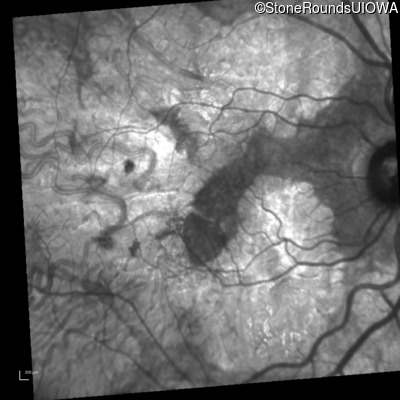

Infrared Fundus Photograph - Right - 20/40 -2

Exemplar

Infrared Fundus Photograph - Left - 20/40 +1